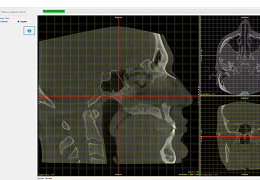

The HNA app opens to the first function tab, which is the Align tab. This provides a way to realign the volume if it wasn’t lined up precisely as desired during the scan procedure.